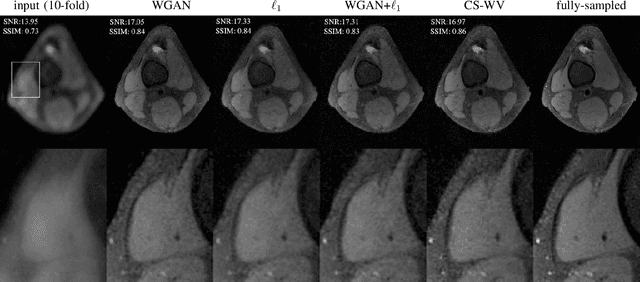

Lack of ground-truth MR images (labels) impedes the common supervised training of deep networks for image reconstruction. To cope with this challenge, this paper leverages WGANs for unpaired training of reconstruction networks, where the inputs are the undersampled naively reconstructed images from one dataset, and the outputs are high-quality images from another dataset. The generator network is an unrolled neural network with a cascade of residual blocks and data consistency modules. The discriminator is also a multilayer CNN that plays the role of a critic scoring the quality of reconstructed images. Our extensive experiments with knee MRI datasets demonstrate unpaired WGAN training with minimal supervision is a viable option when there exists insufficient or no fully-sampled training label images that match the input images. Also, supervised paired training with additional WGAN loss achieves better and faster reconstruction compared to wavelet-based compressed sensing.